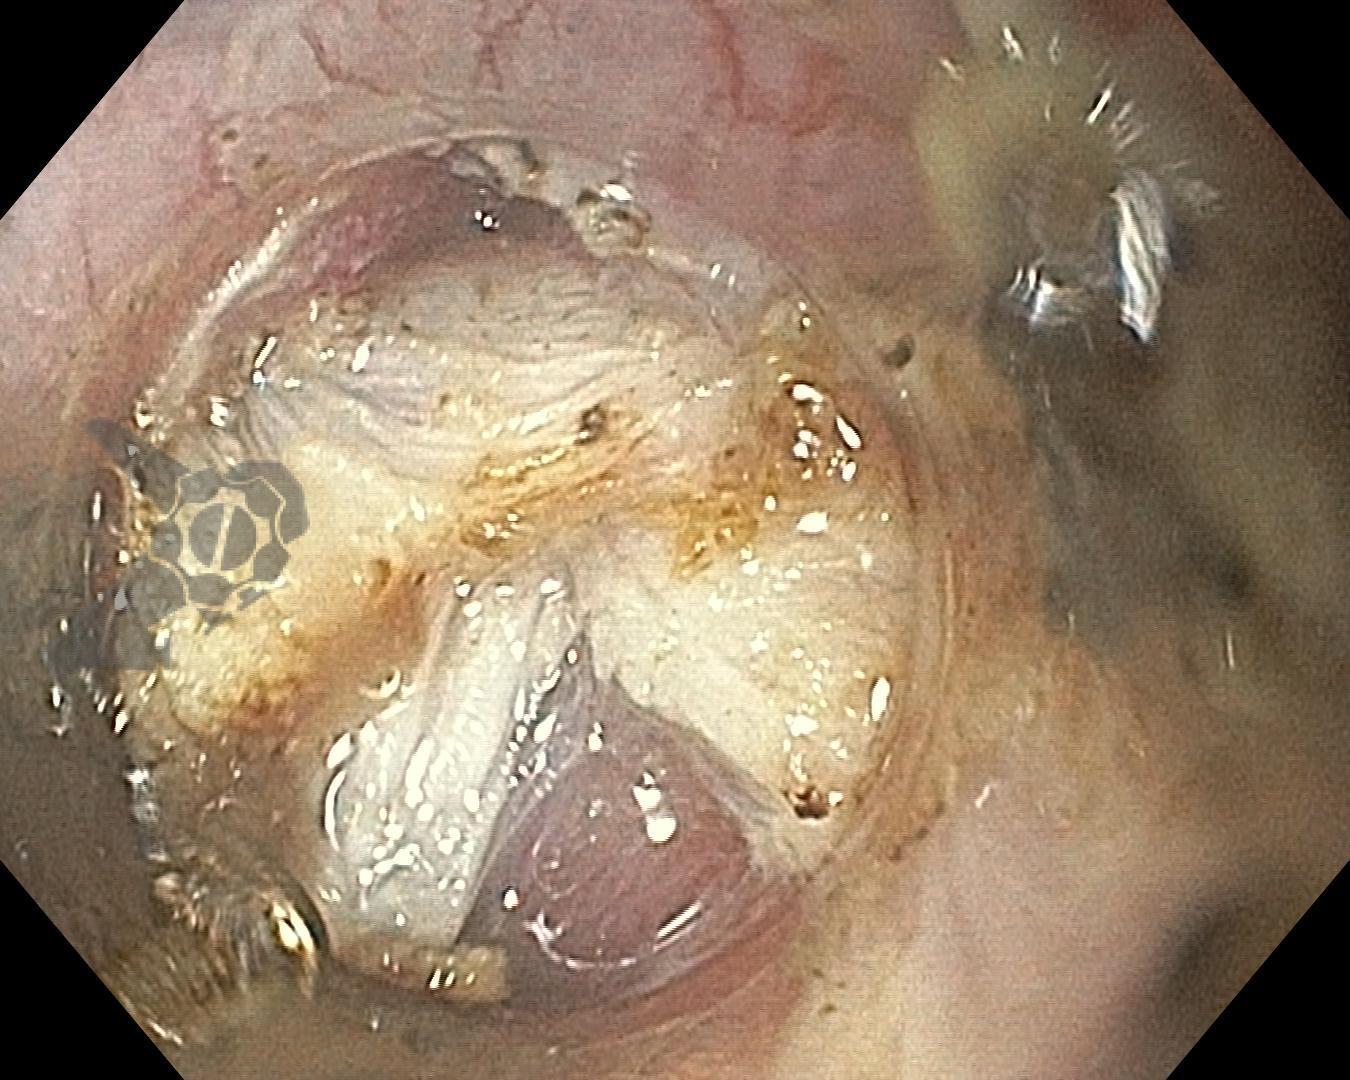

- POEM: miotomia posterior (pela miotomia prévia anterior). Uso de IBP similar ao descrito na DP e posterior de acordo com os sintomas (Fig. 2).